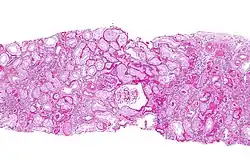

| Micrograph of chronic allograft nephropathy. PAS stain. | |

The histopathology is characterized by interstitial fibrosis, tubular atrophy, fibrotic intimal thickening of arteries and glomerulosclerosis.[2][3]

CAN is diagnosed by examination of tissue, e.g. a kidney biopsy.[4]